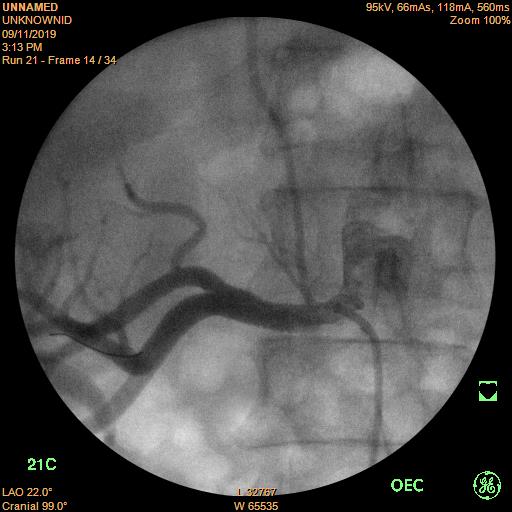

Hình 1. Hẹp 95% động mạch thận phải.

Bệnh nhân vào bệnh viện Trường Đại học Y dược Huế do chấn thương thành ngực, đụng dập phổi, được điều trị tích cực tại khoa ngoại Chấn thương chỉnh hình, được hội chẩn điều trị hạ huyết áp từ khoa nội Tim mạch nhưng vẫn chưa kiểm soát được huyết áp cho dù tình trạng cấp tính do chấn thương đã dần ổn định. Nhận định đây là một trường hợp bệnh lý tăng huyết áp khó, có nhiều bệnh kèm phức tạp, khoa nội Tim mạch đã nhận bệnh điều trị và làm thêm các xét nghiệm chuyên sâu để tìm nguyên nhân gây tăng huyết áp khó kiểm soát ở bệnh nhân này. Sau khi chụp cắt lớp vi tính (CTscan) bụng có thuốc cản quang và chụp mạch máu thận (chụp DSA), bệnh nhân được xác định hẹp 95% đoạn gần gốc động mạch thận phải, động mạch thận trái bình thường.

Sau khi hội chẩn, kíp can thiệp đã quyết định đặt stent (giá đỡ bằng kim loại) để nong vị trí hẹp, do kích thước động mạch thận phải rất lớn nên đơn vị can thiệp tim mạch bệnh viện Trường Đại học Y Dược Huế đã chọn stent động mạch thận phải lớn nhất là 7mm, vị trí đặt khá khó do gần gốc động mạch thận. Sau khi đặt stent kích thước động mạch thận phải trở lại bình thường.

Sau khi nong bằng bóng để làm nở vị trí hẹp, một stent kích thước 7.0x19 mm được đặt vào vị trí hẹp, chụp mạch máu thấy dòng chảy tốt, vị trí hẹp động mạch thận trước đây đã trở lại kích thước bình thường.